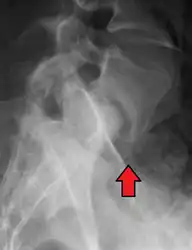

X-ray picture of a grade 1 isthmic anterolisthesis at L4-5

- Isthmic anterolisthesis (a.k.a. type 2) is caused by a defect in the pars interarticularis but it can also be seen with an elongated pars.

Isthmic anterolisthesis is where there is a defect in the pars interarticularis.[34] It is the most common form of spondylolisthesis; also called spondylolytic spondylolisthesis, it occurs with a reported prevalence of 5–7 percent in the US population. A slip or fracture of the intravertebral joint is usually acquired between the ages of 6 and 16 years, but remains unnoticed until adulthood. Roughly 90 percent of these isthmic slips are low-grade (less than 50 percent slip) and 10 percent are high-grade (greater than 50 percent slip).[31] It is divided into three subtypes:[35]

- A: pars fatigue fracture

- B: pars elongation due to multiple healed stress effects

- C: pars acute fracture